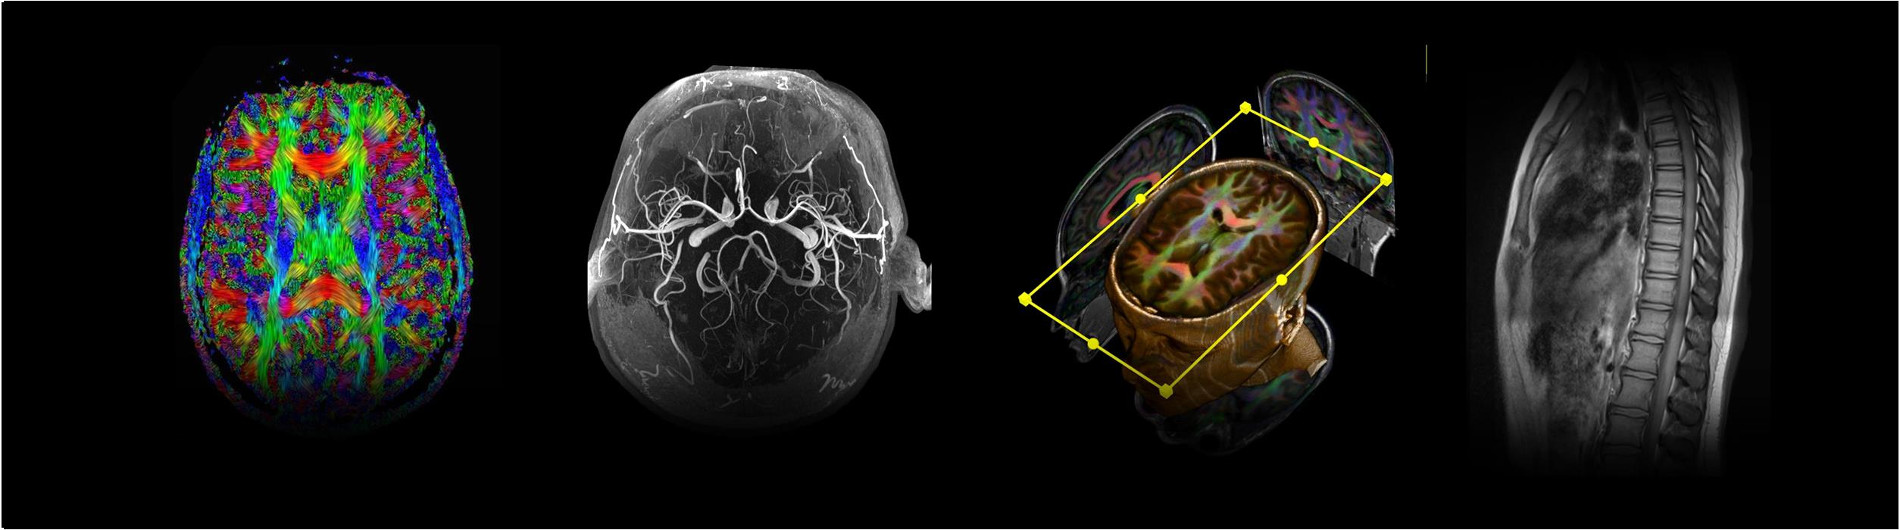

CINL is located on the first floor of UAB Hospital-Highlands. The 5,000 sq. ft. facility houses a Siemens Prisma 3.0T whole body MRI system and a GE Premier 3.0T whole body MRI system for structural, functional, and spectroscopic imaging. Click the button below to learn learn more.

Research at the lab ranges from basic MRI engineering and physics to multisite clinical trials. We support investigators with advanced imaging of the whole body, including the brain, spinal cord, eye, liver, skeletal muscle, and kidney.